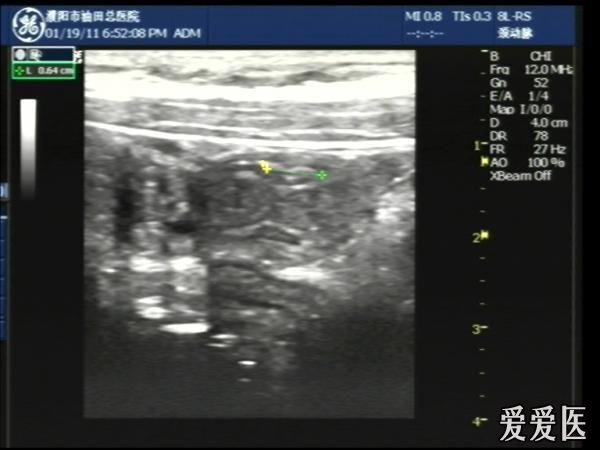

晚6点半,儿童、腹痛5日,无明显压痛及反跳痛。

超声检查:于下腹部可见“双环征象”,双环重叠长约6mm,检查期间观察可见肠蠕动;CDFI:未见明显异常血流信号。

超声提示:下腹部双环征,考虑肠套叠可能,请结合临床

“套筒征”、“同心圆征”,很清晰,很经典!

好图,同心圆征。清晰